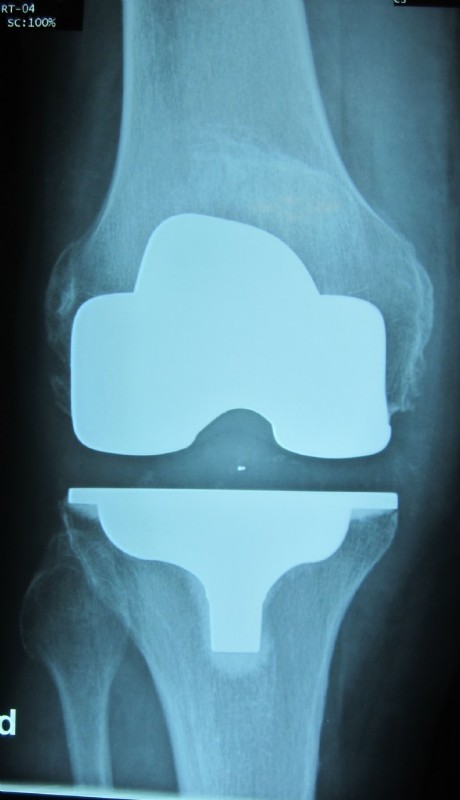

Example of a complete prosthesis

Metal parts are implanted on the thighs and plastic parts on the lower leg, which are embedded in metal components.<br></br>Plastic is also used on the rear surface of the patella with or without a metal bed.<br></br>The implant parts are anchored by either bone cement or in the case of good bone quality also without cement.

For some time, we are now using the so-called "custom made" prostheses. These implants are pre-navigated. This means that our patient is subjected to a CT in addition to the usual X-ray examination. This data is then sent to the U.S., where the company Wright Medical prepares a prosthesis within 3 to 4 weeks and exact cut blocks that fit entirely on the particular patient's knee. Thus, the prosthesis can be used in the operating room as precise as never before and the surgery time is reduced significantly. The improved fitting precision leads to virtually no more axis errors. One must also no longer drill the bones, thus minimizing blood loss and reducing the risk of fat embolism. The surgery can be done gently. The better fit furthermore promises a longer durability of the prosthesis.